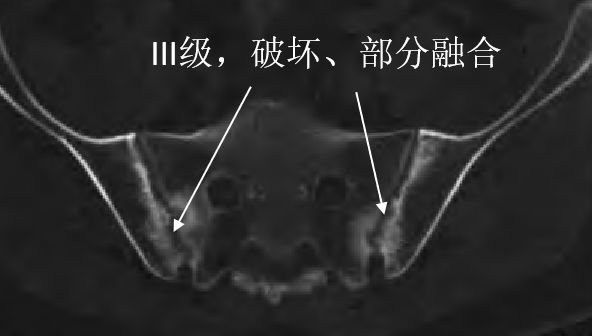

III级破坏的就更明显了,有的地方有侵蚀,有的地方硬化,有的地方狭窄、融合:

III级,破坏,部分融合